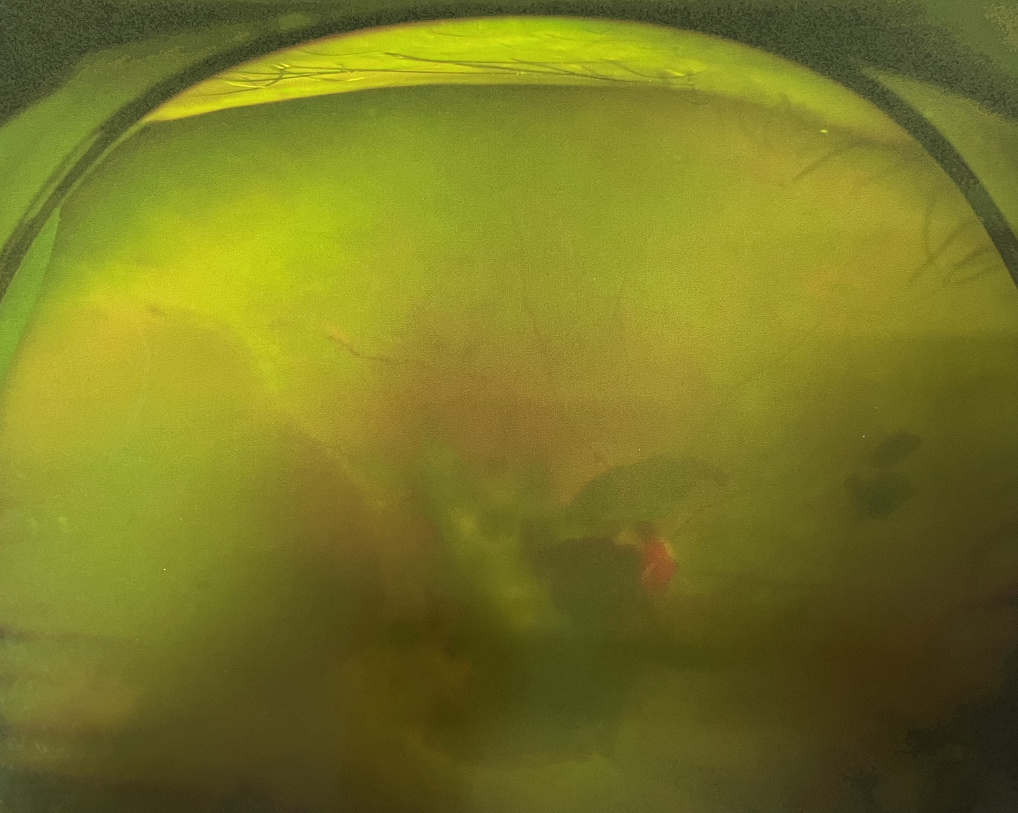

右眼術(shù)前

眼底病??茝埿』⑨t(yī)生檢查后,診斷王女士為“雙眼玻璃體積血、雙眼糖尿病視網(wǎng)膜病變V期”。(V期即5期,纖維增生期,出現(xiàn)纖維膜,可伴視網(wǎng)膜前出血或玻璃體出血。)

張小虎醫(yī)生為王女士進(jìn)行右眼玻璃體腔注藥術(shù),3天后進(jìn)行右眼23G玻璃體切割術(shù)后視力有所提升。

張小虎醫(yī)生表示,糖網(wǎng)病進(jìn)展到嚴(yán)重增殖期帶來的視力損傷往往是極其嚴(yán)重的,目前王女士右眼從術(shù)前0.02恢復(fù)到術(shù)后0.6,已屬十分難得。